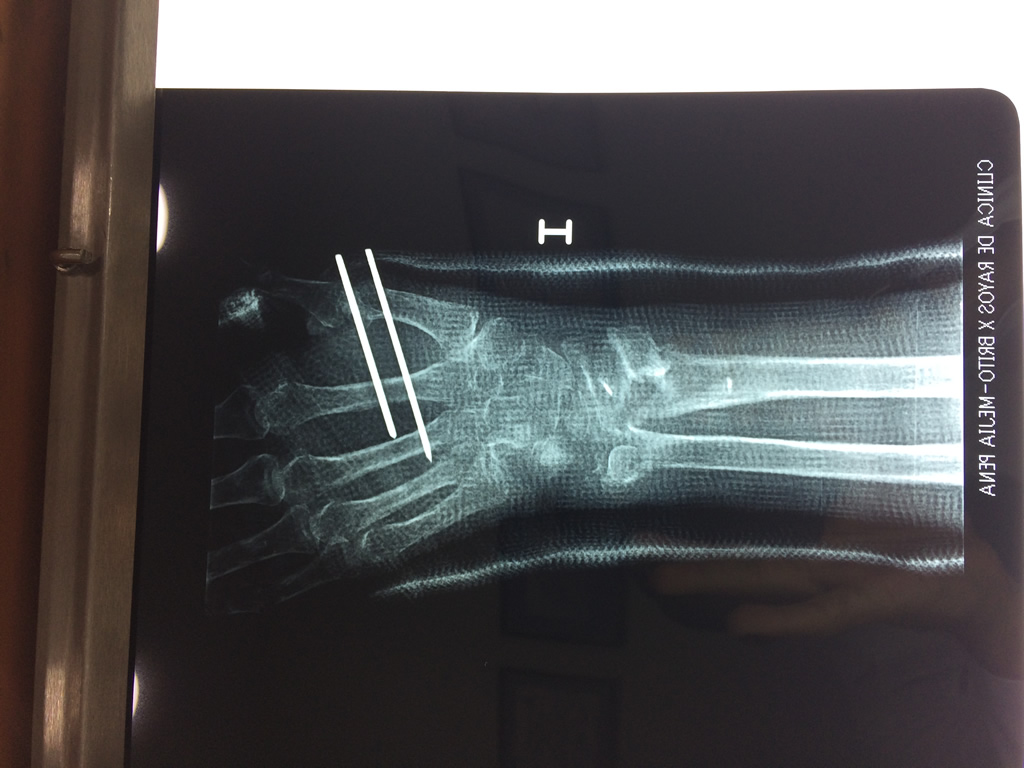

Cirugías de Húmero - Cirugías de Muñecas y Manos

Los procedimientos más comunes en cirugía de la mano son aquellos destinados a reparar traumatismos, incluyendo lesiones de tendones, nervios, vasos sanguíneos, y articulaciones; huesos fracturados; y quemaduras, cortes, y otros daños de la piel.